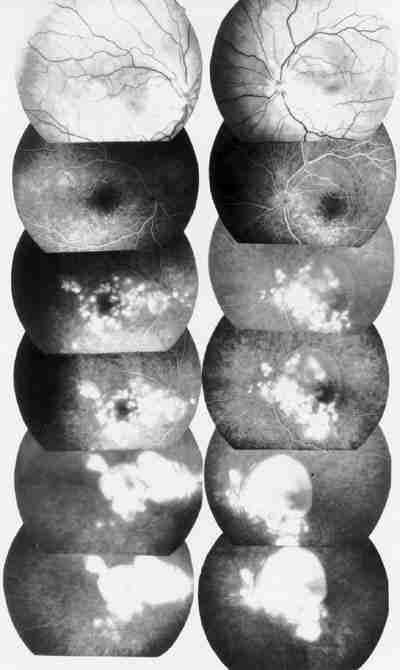

Figura 3

f07-03.jpg (55870 bytes)